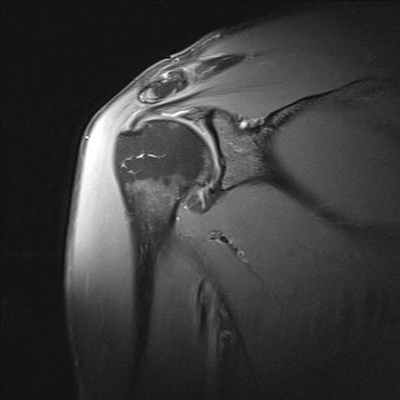

Разрывы вращательной манжеты плеча являются наиболее частой причиной болевого синдрома в плечевом суставе во всех возрастных группах взрослого населения и невозможности поднять или отвести руку. МРТ диагностика при данной травме позволяет визуализировать как полный разрыв связок, так и частичное их повреждение. Как правило, сопутствующими осложнениями повреждений вращательной манжеты плеча является скопление жидкости в субакромиальной и поддельтовидной сумках (находятся между мышцами), что также хорошо выявляется при МРТ исследовании. А восстановление разрыва сухожилий вращательной манжеты является сложной хирургической операцией.

МРТ признаки повреждения акромиально-ключичного сочленения на уровне плечевого сустава

МРТ плечевого сустава